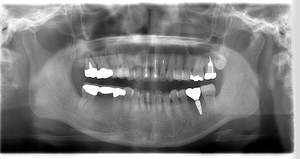

インプラント治療の症例2

レントゲン写真

- Befor

- After

| 年齢 | 50代・男性 |

|---|---|

| 主訴 | 左上7番 左下5番7番 |

| 治療内容 | ・インプラント埋入 ※1:GBR(骨造成)・・・骨再生誘導法。骨の高さや厚みを人工骨や人工膜などを使用し再生する方法 |

| 治療費 | 合計:1,809,500円(税込) ■内訳 ・左上7番 ・左下5番7番 |

| 治療期間 | 左上7番約1年 左下5番7番約10ヵ月 |

| 治療方針 | 左上7番は昔他院で被せものをしており、被せものの中が歯ぐきの中まで虫歯になっていたため抜歯せざるを得ない状態だった。抜歯と同時に骨造成を行い、骨が出来るまで4ヵ月待ってからインプラントを埋入した。 ※2ポンティック・・・歯のない部分を補うダミーの歯。 |

| 担当者所見 | 元々金属の被せものが多く入っていたため、2次カリエス※3が多かった。今回は金属ではなく、ジルコニアを使用し、2次カリエスにならないよう、患者様にはブラッシング指導とメンテナンスの重要性をお伝えした。 ※3二次カリエス・・・詰め物や被せものを入れた歯が虫歯になること。 |